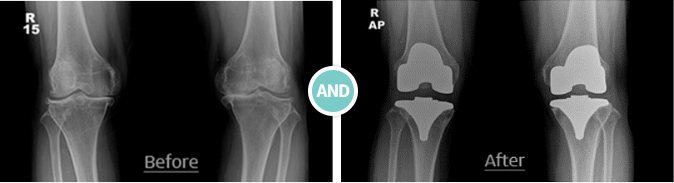

무릎 인공관절 전치환술(TKR)

인공관절 전치환술은 말 그대로 관절 전체를 인공관절로 대체하는 수술입니다.

퇴행성 관절염으로 마모가 심각한 환자의 경우, 관절의 변형으로 보행 장애와 극심한 통증에 시달리게 되어

일상생활에 지장이 생길 정도이므로 반드시 치료가 필요합니다. 이때, 관절 전체를 대체하여 관절염의 진행을 막고

통증을 완화시켜 관절이 정상적으로 가능하게 하여 일상생활이 수월하도록 돕습니다.

X-선 검사에서 말기 퇴행성 관절염인 경우인 환자분들에게 권장합니다.

수술 후 가장 좋아지는 것은 수술 전에 보행시 있던 극심한 통증이 사라지고 변형이 교정되어 일상생활로의 복귀가 가능해집니다.

수술 후 3일째부터 보행기나 양축 목발을 이용하여 보행이 가능하고, 수술 후 3개월에는 지팡이 없이 대부분 정상 보행을 할 수 있습니다.